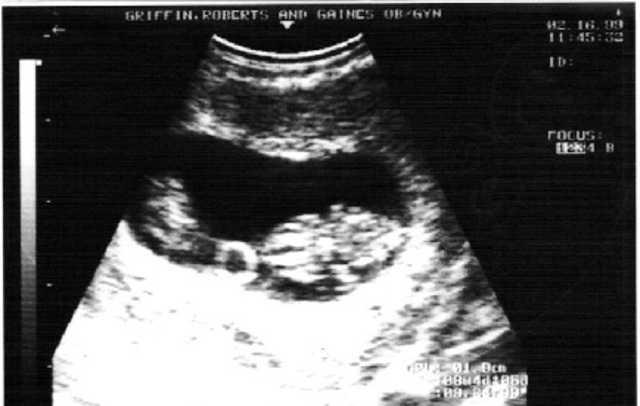

• Eyelids can open and weight can be up to 6.6 pounds.

Eyelids can open and weight can be up to 6.6 pounds.

A fetus between 6 and 9 months after conception can weigh 2.2 pounds. At that age, its eyelids can open. Stockarch, . eye2314. morgueFile. Web. 17 Feb. 2012.